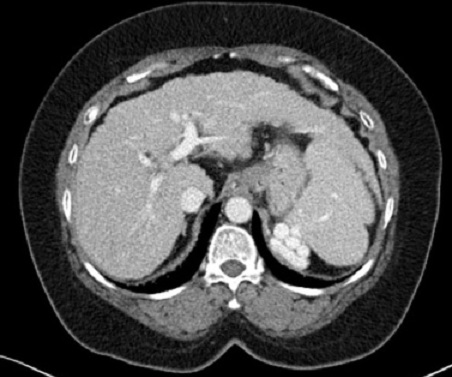

Image

radiologique TDM d'une cirrhose du foie en coupe

axiale . Le parenchyme et surface du foie est en

nodulaire , heterogene . La lobe caude est

hypertrophie , splenomegalie legere . Index C/RL est

> 0.66 ( cirrhose du foie ) |

Index C/RL : Coupe axiale TDM

a inferieure de bifurcation de la veine porte

.

| C : distance entre line1et

line2 |

| RL:distance entre line1 et bord

externe du foie |

| C/RL < 0.6

= foie normale |

| C/RL = 0.6 - 0.65 =

bordeline de cirrhose |

| C/RL >

0.65 = 96% est cirhose du foie |

0.73 = 99% est cirhose du foie |